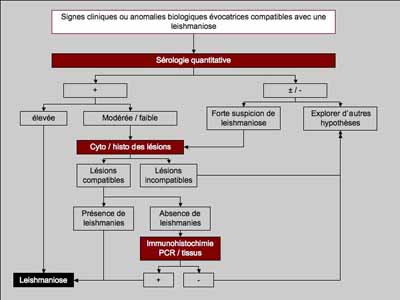

Lorsque les lésions sont riches en éléments parasitaires, le Diagnostic histologique de leishmaniose ne pose pas de problème particulier, mais lorsque le patron lésionnel est moins classique (dermatite périvasculaire pustuleuse acantholytique ou non, ou vascularite) et /ou lorsque les lésions sont pauci-parasitaires, l’examen histologique arrivera difficilement à un diagnostic de certitude, mais plutôt à une forte suspicion histologique de leishmaniose cutanée : il faudra alors compléter l’examen histologique par d’autres examens complémentaires [Photo 23 démarche diagnostique conseillée par LeishVet guidelines for the pratical management of canine leishmaniosis, 2011 (6,7)].

Photo 23 : Démarche diagnostique de la leishmaniose canine

d’après Solano-Gallego et al : LeishVet guidelines (6,7)